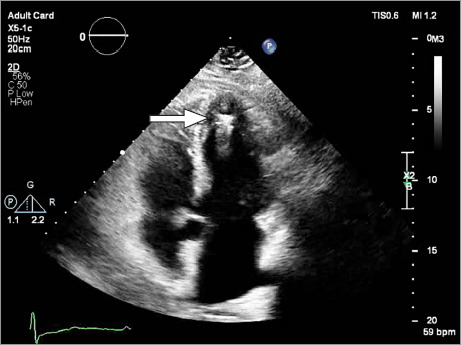

Micra装置是一种通过股静脉经导管入路植入右心室的无铅起搏器。使用无导线起搏器有几个适应症和优点,该设备在心脏病学领域的作用可能会继续增加。这篇文章提出了一个罕见的并发症的情况下,可能是由于无意中放置装置在左心室跨越一个未确诊的卵圆孔未闭。

The Micra device is a leadless pacemaker implanted in the right ventricle via a femoral vein transcatheter approach. There are several indications for and advantages to using a leadless pacemaker, and the device's role in the field of cardiology will probably continue to increase. This article presents the case of a rare complication probably due to inadvertent placement of the device in the left ventricle across an undiagnosed patent foramen ovale.